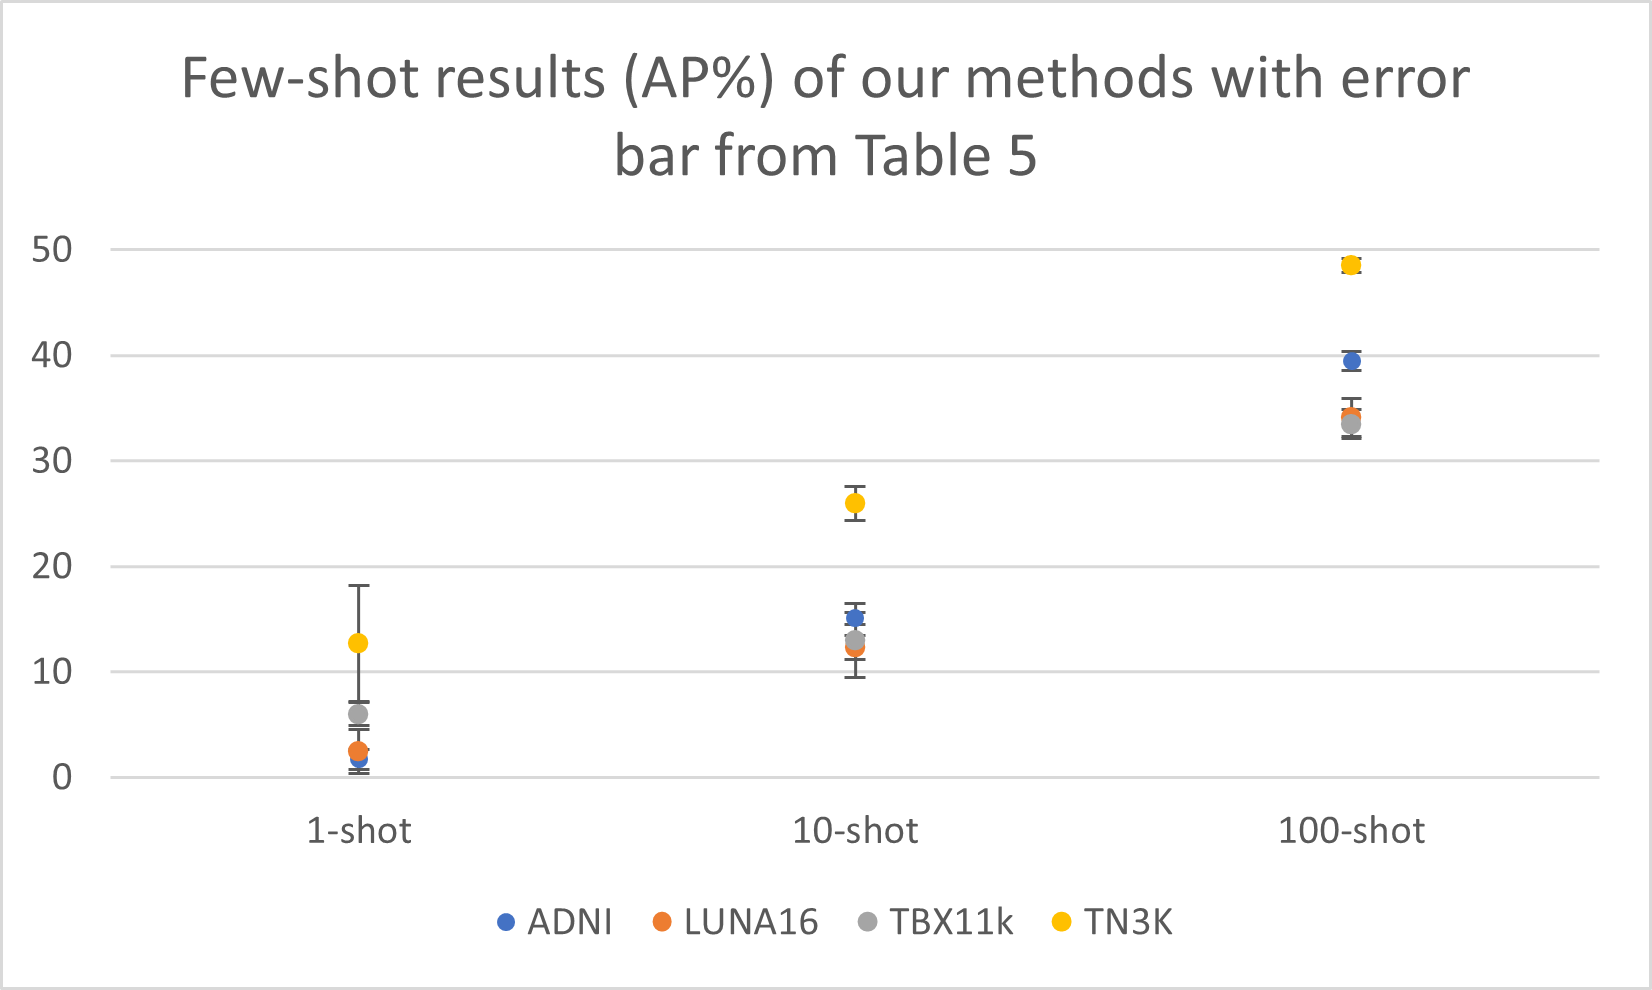

Fine-tuning on radiology datasets We finally evaluate the fine-tuned models on the radiology datasets under different few-shot settings, i.e., 1-shot, 10-shot, 100-shot, as well as full-data fine-tuning. The results are presented in Table 5. As we can see from the numbers, the overall performance of our fine-tuned models is much better than that of the supervised baselines, consistent with the findings in non-radiology medical images. This property reveals itself extremely in the 1-shot experiments. The average AP across all datasets of our models reaches 5.7 %AP, while other baselines give 0% AP. As the training data increases from zero-shot to full-size, the performance gap gets narrower. According to this pattern, we conclude that the pre-trained VLMs like GLIP is more data efficient than the traditional supervised baselines. Given the medical image data’s scarcity, we believe the data efficient property of VLMs would benefit many medical scenarios.

In this section, we demonstrate the standard deviation numbers and error-bar for our fine-tuning results. We use 3 different random seeds for our few-shot learning experiments to test whether our fine-tuning results are consistent across different random settings. The relative small standard deviation indicates that our method is not sensitive to the randomness.

TBX11K Luna16 ADNI TN3k Avg. AP AP50 AP AP50 AP AP50 AP AP50 AP AP50 1-Shot 5.7 14.0 10-Shot 16.6 41.2 100-Shot 38.9 76.7